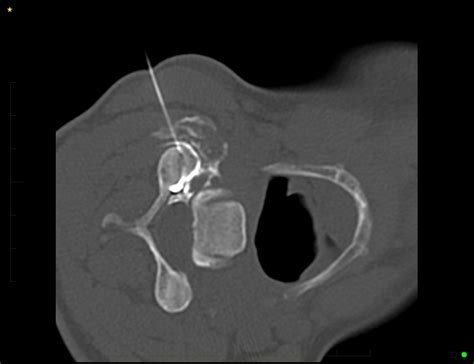

• Guidance: Using real-time X-ray guidance, known as fluoroscopy, the doctor carefully guides a thin needle toward the facet joint.

• Injection: Once the needle is in the correct position, a contrast dye may be injected to verify placement, followed by the therapeutic medication.